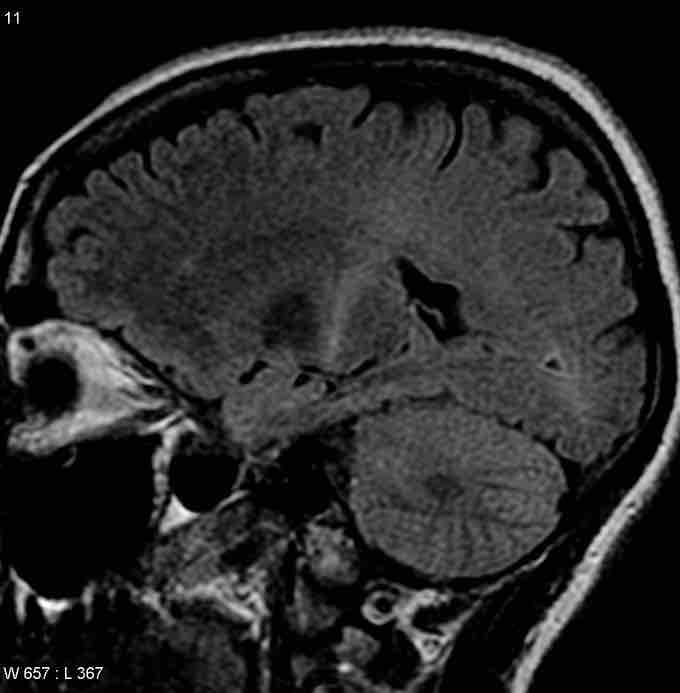

Coronal MRI of an ALS patient

MRI (parasagittal FLAIR) demonstrates increased T2 signal within the posterior part of the internal capsule and can be tracked to the subcortical white matter of the motor cortex, outlining the corticospinal tract), consistent with the clinical diagnosis of ALS.